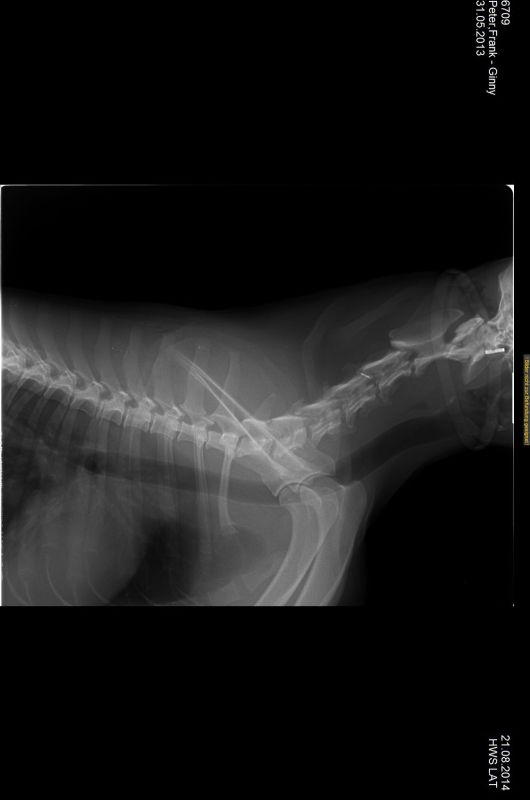

21.08.2014 - Ginny HD-und ED geröntgt - 15 Monate alt